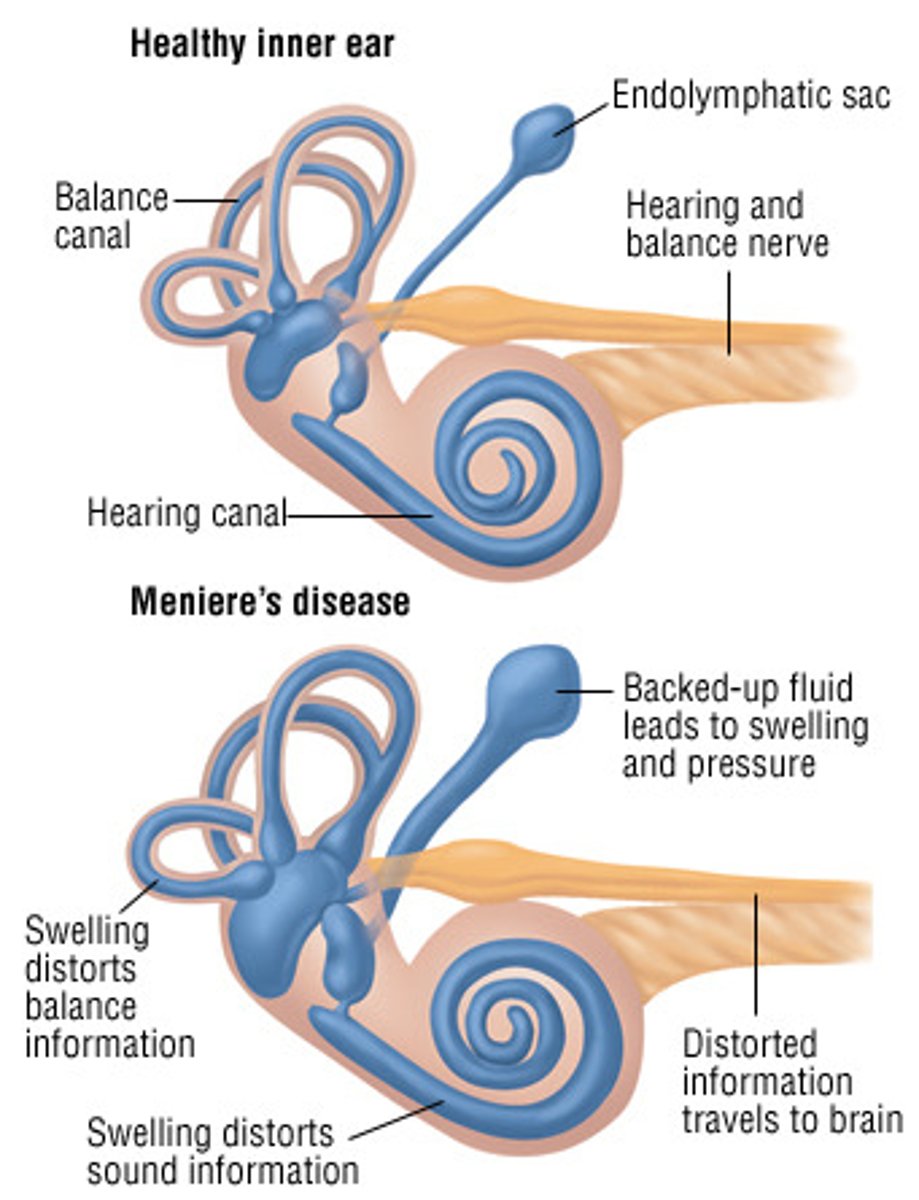

Episodic vertigo, tinnitus, hearing loss

Meniere disease:

excess of endolymph fluid in the inner ear